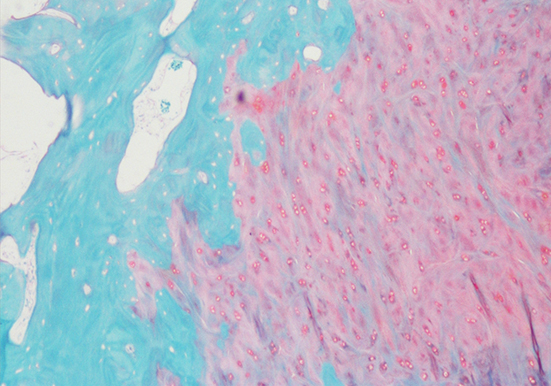

番红-固绿染色(软骨)在涉及关节软骨及软骨下骨的形态学研究中,常需联合使用多种染料以显示其组织学结构。其中,起源于上世纪60年代的番红O(safranin O)-固绿(fast green)染色因可以直观反映关节软骨、软骨下骨和骨组织的结构而备受青睐。软骨呈红色,成骨呈绿色。

番红-固绿(软骨)染色法的染色原理在于嗜碱性的软骨和碱性染料番红O结合呈现红色,嗜酸性的骨和酸性染料固绿结合而成绿色或者蓝色,与呈现红色的软骨对比鲜明,从而将软骨组织和骨组织区分开。番红O是一种结合多阴离子的阳离子染料,其显示软骨组织是基于阳离子染料与多糖中阴离子基团(硫酸软骨素或硫酸角质素)结合。番红O着色与阴离子的浓度近似成正比关系,间接反映基质中蛋白多糖的含量和分布。当软骨收到损伤时,软骨中的糖蛋白会释放出来,使基质成分分布不均匀,从而导致番红O淡染或不着色。通过图像分析软件可以对番红O染色的软骨基质进行定量分析。固绿与胶原纤维结合,不宜褪色。

实验结果展示:

番红固绿-骨>